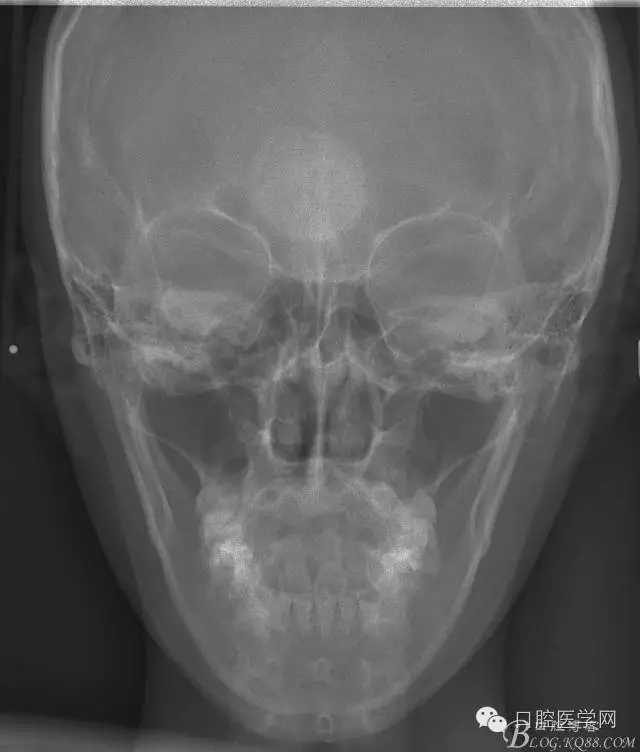

正畸查:替牙合。第一恒磨牙中性合。上牙弓尖圓型下牙弓方圓型。前牙覆合3度覆蓋7.5mm。下前牙咬到上舌側(cè)牙齦。上頜擁擠4.0mm,下頜擁擠

3.0mm。上頜稍前突下頜后縮,上下唇前突,上前牙覆蓋下唇,下唇外翻。面下三分之一過(guò)短,頦唇溝明顯,開(kāi)唇露齒,頦饜窩明顯。顳下頜關(guān)節(jié)開(kāi)閉口無(wú)彈響,無(wú)壓痛,開(kāi)口型開(kāi)口度正常。